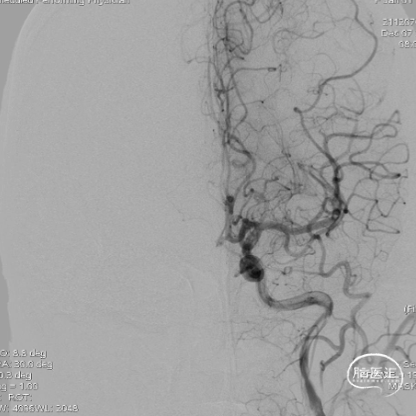

术前造影:提示左侧颈内动脉起始段闭塞,左侧大脑后动脉后交通开放,代偿左侧大脑中动脉部分供血区。

术后造影:

术后造影及CT提示:左侧颈内动脉开通,血流灌注达mTICI 2c级,造影剂无外渗,远端分支血管部分闭塞。